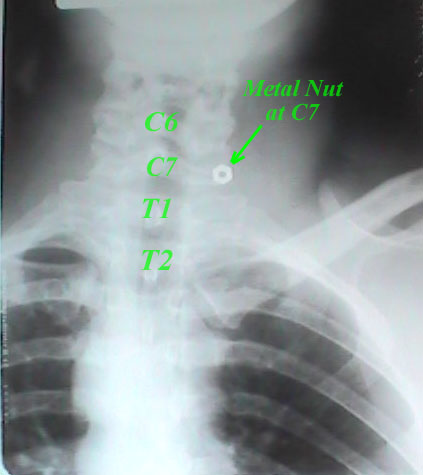

The metal nut is seen at C7, not T1, 2 or 3. Interestingly enough, if you looked closely, my shirt 'bunched' up just below the collar. Why? Simple. When you elevate your shoulders, the fabric lying on top moves, too. The collar is a thicker portion of fabric that is creased and folded down. The shirt fabric, when elevated in such a manner, is 'pushed down' (for a lack of a better phrase) by the collar's bottom edge and a fold of 'bunched' fabric is created. See the following video clip by clicking here. Now, next time you are talking to someone who is wearing a dress shirt and tie or a sport coat, and they are sitting, take note to what the fabric is doing. Chances are that you'll see the 'bunch' phenomenon happen before your very eyes- you just never noticed it before. You can also witness this during just about any movie at Hollywood Video or Blockbuster.